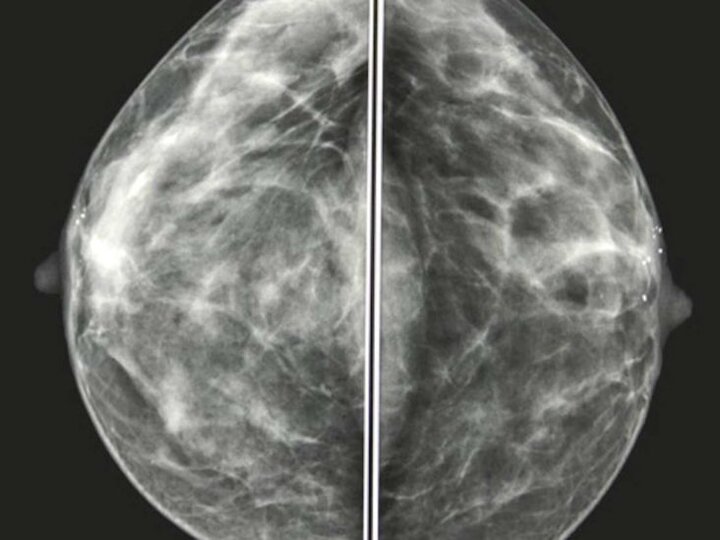

بافت نرمال سینه

سینهها حاوی چربی، همراه با بافت فیبری و غدهای هستند. هرچه بافت فیبروگلاندولار بیشتری داشته باشید، سینههای شما چگالتر است. رادیولوژیست، تراکم سینه شما را با استفاده از چهار دسته طبقه بندی میکند:

وقتی قسمت اعظم سینهها چرب باشند، بافت روی ماموگرافی تیره و شفاف است. این کار تشخیص ناهنجاریها را که به طور کلی با رنگ سفید نشان داده میشود، آسان میکند.

بافت متراکم سینه در ماموگرافی سفید به نظر می رسد. تومورها و سایر توده ها نیز سفید به نظر می رسند، بنابراین تشخیص ناهنجاریها دشوارتر میشود. بسیاری از زنان، سینه متراکم دارند. معمولا، اما نه همیشه، با افزایش سن، سینههای شما تراکم کمتری پیدا میکنند.